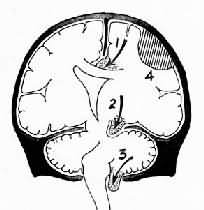

二、常见的并发症中枢神经系统疾病最常见而重要的并发症为颅内压升高、脑水肿和脑积水,其中脑水肿和脑积水可引起或加重颅内压升高,三者可合并发生,互为因果,后果严重可导致死亡。 (一)颅内压升高及脑疝形成 侧卧位的脑脊液压超过2kPa(正常为0.6~0.8kPa)即为颅内压增高,这是由于颅内容物的容积增加,超过了颅腔所能代偿的极限所致。颅内压增高的主要原因是颅内占位性病变和脑脊液循环阻塞所致的脑积水。常见的占位性病变为脑出血和血肿形成(如创伤、高血压脑出血等),脑梗死,肿瘤,炎症(如脑膜脑炎、脑脓肿等),脑膜出血等。其后果与病变的大小及其增大的速度有关。脑水肿可加重病变的占位性。颅内压升高可区别为3个不同的时期: 1.代偿期通过反应性血管收缩以及脑脊液吸收增加和形成减少,使血容量和脑脊液容量相应减少,颅内空间相对增加,以代偿占位性病变引起的脑容积增加。 2.失代偿期占位性病变和脑水肿使颅内容物容积继续增大,超过颅腔所能容纳的程度,可引起头痛、呕吐、眼底视乳头水肿、意识障碍、血压升高及反应性脉搏变慢和脑疝形成。 3.血管运动麻痹期颅内压严重升高使脑组织灌流压降低,致脑缺氧造成脑组织损害和血管扩张,继而引起血管运动麻痹,加重脑水肿,引起昏迷及并发症,后果严重,可导致死亡。 升高的颅内压可引起脑移位、脑室变形、使部分脑组织嵌入颅脑内的分隔(大脑镰,小脑天幕)和颅骨孔道(如枕骨大孔等)导致脑疝形成(herniation)。常见的脑疝有以下类型。 1.扣带回疝又称大脑镰下疝,是因一侧大脑半球特别是额、顶、颞叶的血肿或肿瘤等占位性病变,引起中线向对侧移位,同侧扣带回从大脑镰的游离边缘向对侧膨出,形成扣带回疝。疝出的扣带回背侧受大脑镰边缘压迫形成压迹,受压处的脑组织发生出血或坏死。此外,大脑前动脉的胼胝体支也可受压引起相应脑组织梗死。大脑冠状切面上可见对侧的侧脑室抬高,第三脑室变形,状如新月(图16-6)。

图16-6 脑疝模式图 1.扣带回疝;2.海马钩回疝;3.小脑扁桃体疝;4.硬膜外血肿 2.小脑天幕疝又称海马钩回疝。位于小脑天幕以上的额叶或颞叶内侧的肿瘤、出血、梗死等病变引起脑组织体积肿大,导致颞叶的海马钩回经小脑天幕孔向下膨出。海马钩回疝可导致以下后果:①同侧动眼神经在穿过小脑天幕裂孔处受压,引起同侧瞳孔一过性缩小,继之散大固定,及同侧眼上视和内视障碍。②中脑及脑干受压后移,可导致意识丧失;导水管变狭,脑脊液循环受阻加剧颅内压的升高;血管牵伸过度,引起中脑和桥脑上部出血梗死,可导致昏迷死亡。③中脑侧移,使对侧中脑的大脑脚抵压于该侧小脑天幕锐利的游离缘上,形成Kernohan切迹。严重时该处脑组织(含锥体索)出血坏死,导致与天幕上原发病变同侧的肢体瘫痪,引起假定位症。④压迫大脑后动脉引起同侧枕叶距状裂脑组织出血性梗死(图16-7)。